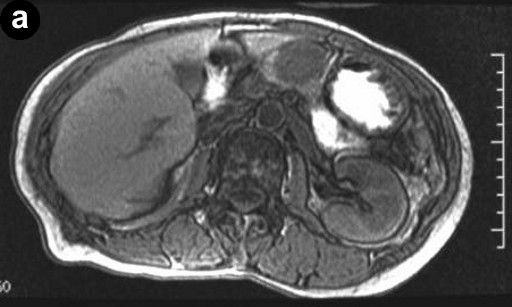

A 66-year-old Japanese woman was admitted to our hospital with a pancreatic tumor indicated in medical examinations. There was no remarkable past history of disease. No inherited factors or marked diseases in her family were noted. On admission, she had no complaints, and physical examinations and laboratory data revealed no noticeable abnormalities. Serum levels of CA 19-9 and s-pancreas-1 (pancreatic associated) antigen were within the normal range. Magnetic resonance imaging (MRI) revealed a mass, 3 cm in diameter, in the body of the pancreas, showing hypointensity on T1-weighted images, marked enhancement after gadolinium diethylenetriaminepenta acetic acid (Gd-DTPA) administration, and mixed hypo- and hyperintense patterns on T2-weighted images (Figure 1abc). Magnetic resonance cholangiopancreatography (MRCP) and endoscopic retrograde cholangiopancreatography (ERCP) showed no abnormal findings. The results of bacterial cultures of the pancreas juice were negative. Computed tomography (CT) revealed a 3 cm solid and cystic tumor within the body of the pancreas, with high resorption CT levels of the cystic components (Figure 1d). Contrast-enhanced CT showed partial enhancement of the solid components, and the main pancreatic duct was not involved in the tumor. Ultrasonography (US) and endoscopic ultrasonography (EUS) revealed a 3 cm solid and cystic tumor with low echoic margins in the body of the pancreas (Figure 2a). Contrast-enhanced US with Levovist® (Bayer Schering, Berlin, Germany) showed partial enhancement of the solid components (Figure 2b). Angiography showed no abnormal findings. From these imaging findings, mucinous cystic neoplasms or acinar cell tumors were considered.

Figure 1a. A T1-weighted MRI indicating a hypointense tumor in the body of the pancreas. b. On T1-weighted images, Gd-DTPA administration showing marked tumor enhancement. c. A T2-weighted MRI indicating a mixed pattern with hypointensity and hyperintensity. d. Plain CT revealing a solid and cystic tumor within the body of the pancreas, with high resorption CT levels of cystic components. |

The MRI findings usually showed hypointensity on T1-weighted images and hyperintensity on T2- weighted images [6, 9], and most tumors were gradually enhanced on T1-weighted images after Gd-DTPA administration. However, the present case was unusual, showing a mixed hypointensity and hyperintensity pattern on T2-weighted images. This can be attributed to the fact that the present tumor included a fair amount of both Antoni A and Antoni B areas, conceivably with the hypointense areas corresponding to the Antoni B areas, and the hyperintense areas to the Antoni A areas.